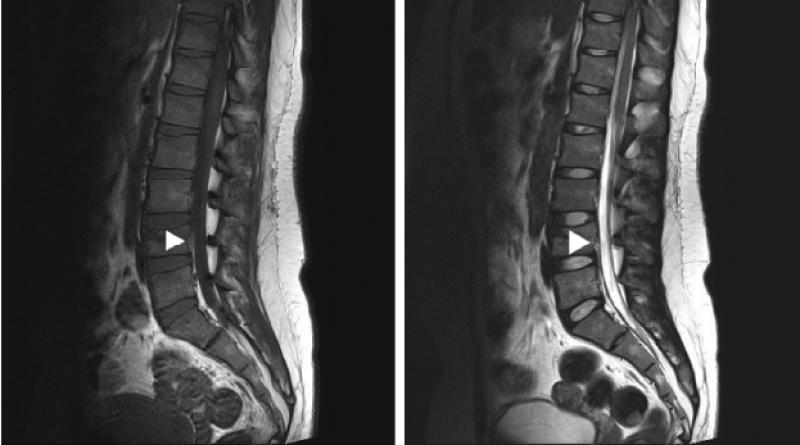

Anterior Epidural Anestezi Nedir?Anterior epidural anestezi, cerrahi işlemler sırasında ağrıyı kontrol altına almak için kullanılan bir anestezi yöntemidir. Bu teknik, spinal kordun etrafındaki epidural alanın hedeflenerek lokal anestezik maddelerin enjekte edilmesiyle gerçekleştirilir. Anterior epidural anestezi, özellikle alt karın, pelvis ve bacak bölgelerinde yapılan cerrahilerde tercih edilir. Anterior Epidural Anestezi Uygulama AlanlarıAnterior epidural anestezi genellikle aşağıdaki durumlarda uygulanmaktadır:

Olgunay, anterior epidural tedavi yöntemi, bel ve sırt ağrıları gibi durumların tedavisinde sıklıkla tercih edilen bir yöntemdir. Bu uygulama sırasında enjekte edilen serum, genellikle anestezik ve steroid içerir. Uygulama sırasında çoğu kişi, anestezik madde sayesinde geçici bir rahatlama hisseder. Ancak bu his kişiden kişiye değişebilir; bazıları hafif bir sıcaklık veya uyuşma hissi yaşayabilir.